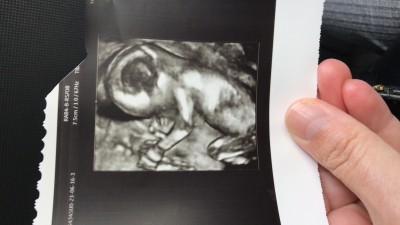

Merhaba hanımlar attigim ultrosyan bacak arası mı acaba bilgisi olan yazarmi acaba

Evet bacak arası yüzde yüz de erkek canım sağlıkla al kucağına inşallah ❤️kendimin ki buda aynısı

bak cizdigim yerlere dikkatli bak senin resmin bacak arası dolu benimkisi boş